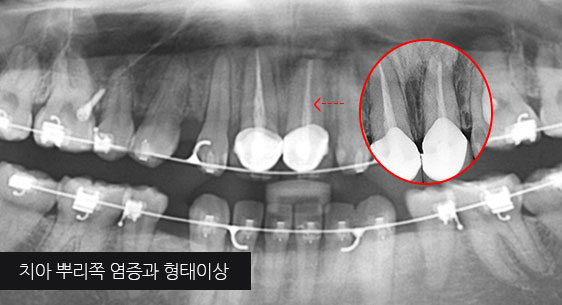

치아 뿌리 주변 염증과 치조골이 녹아내려 통증과 더불어 치아가 흔들리는 상태로 내원한 환자입니다. 우선 큐렛으로 잇몸 속 치석을 제거하였습니다.

뿌리 주변 염증은 신경관을 소독하고 약재를 삽입하는 신경치료를 시행하였습니다.